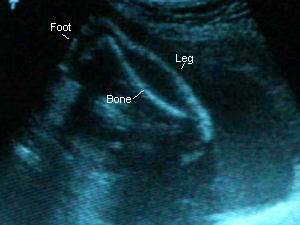

21 Weeks 1 Day

September 21, 2006: I forgot completely to ask the doctor about my AFP results, but since he didn’t mention anything I’m guessing everything’s A-OK. Baby again looks “fuller” than she did at my previous appointment, which was three weeks ago. She’s measuring perfectly and weighs approximately 0.8 lbs :). Her heartrate was at 145 BPM, though the monitor read 155. She was moving around (I got to see her little knees, feet and hands!) and Dr. C. said her head’s where my belly button is and her feet are at the bottom of my pelvis. No wonder I feel strange little jolts down there! I had glucose in my urine for the second time, but after checking me with the diabetes monitor it turns out I’m fine. Must have been the chocolate milk I drank in the morning. I’m feeling her move more after lunchtime and A LOT at 11pm. Mario finally felt her kick on 9-15-06!

Sono pic:

These are from a video I took with my camera. Thank goodness, too, because he didn’t give me pictures this time!